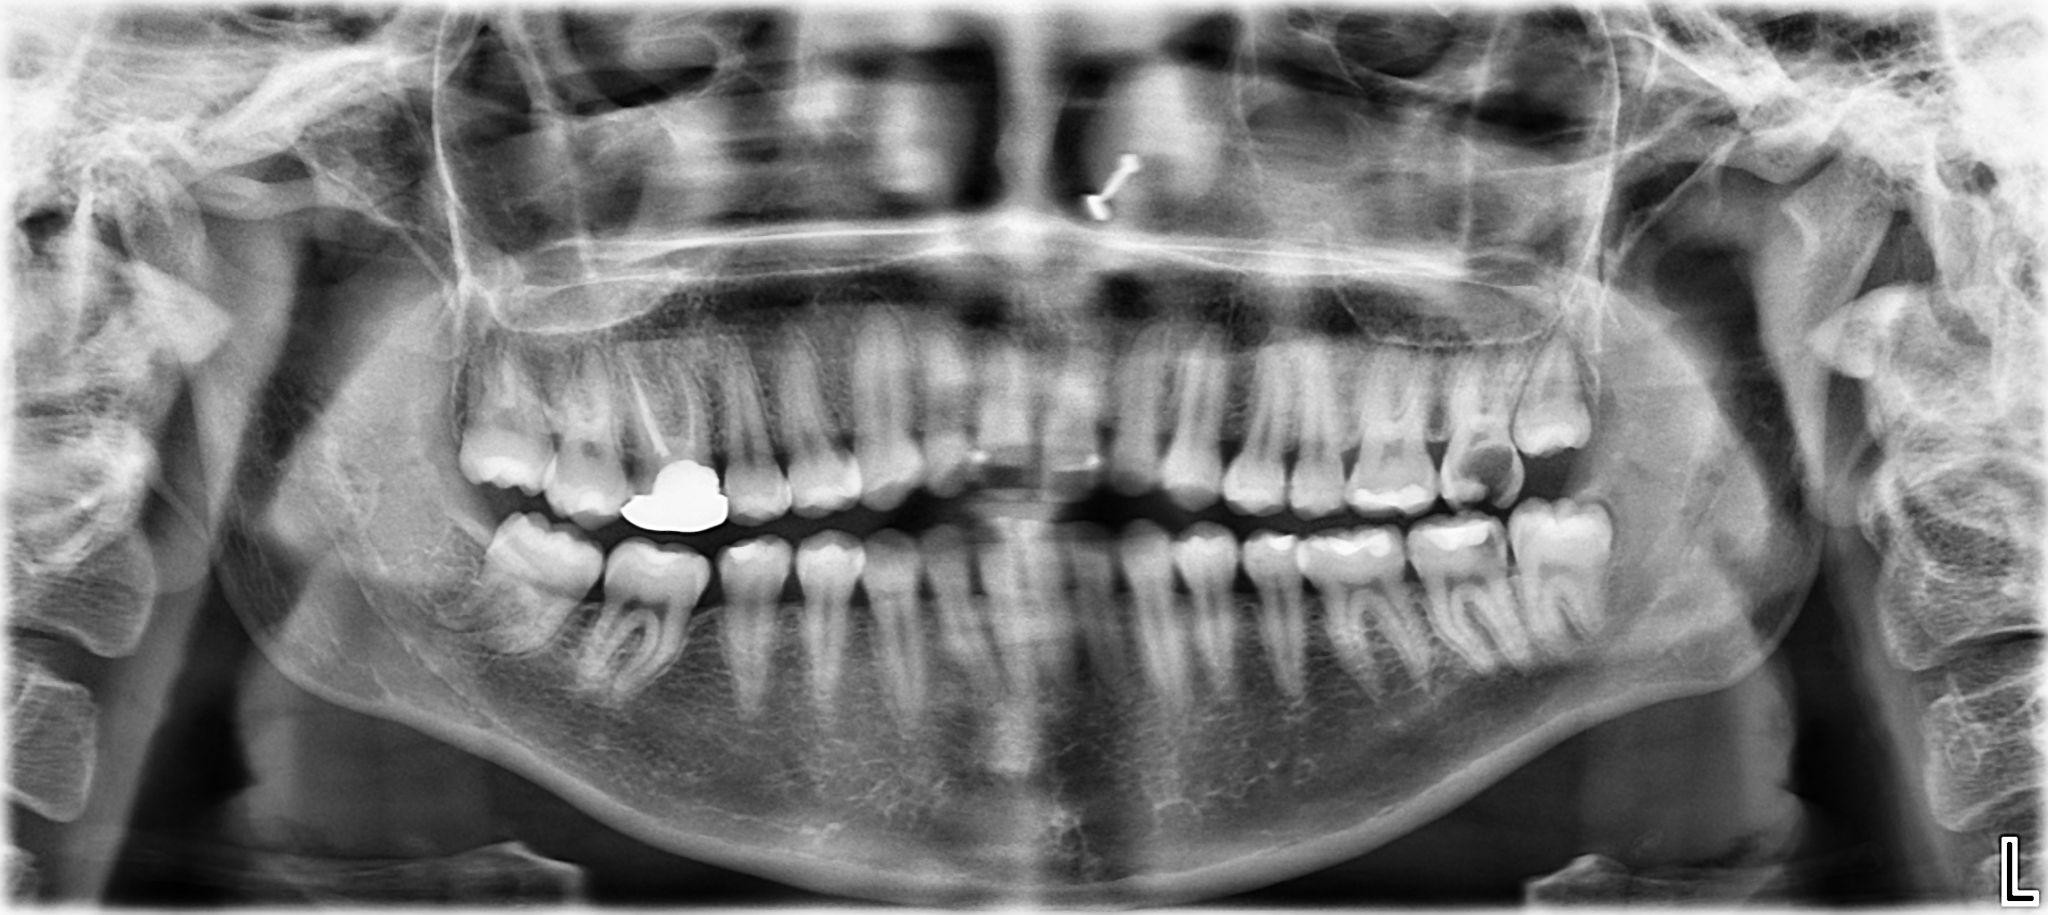

17. What options can be selected for the first quadrant of this panoramic X ray?

18. What options can be selected for the second quadrant of this panoramic X ray?

19. What options can be selected for the third quadrant of this panoramic X ray?

20. What options cannot be selected for the forth quadrant of this panoramic X ray?

21. What options can be selected for the first quadrant of this panoramic X ray?

22. What options cannot be selected for the second quadrant of this panoramic X ray?

23. What options can be selected for the third quadrant of this panoramic X ray?

24. What options can be selected for the forth quadrant of this panoramic X ray?